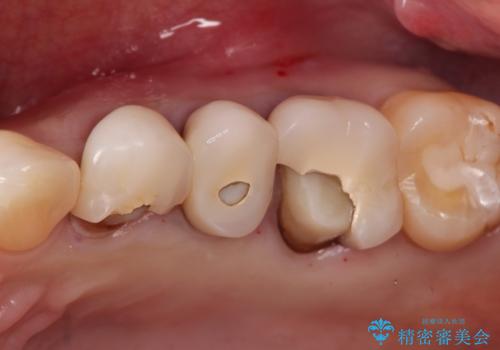

【オールセラミッククラウン】プラスチックの被せ物が壊れた。

- 以前他院で治療した被せ物が壊れたことを主訴に来院されました。

強度に優れたオールセラミッククラウンにて治療を行なっております。